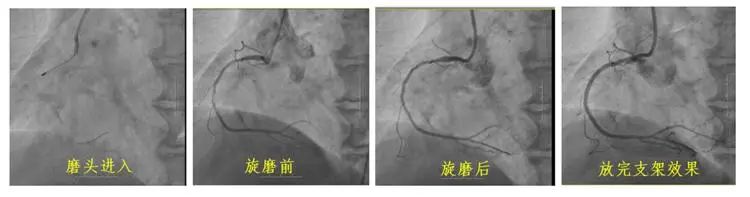

冠狀動脈鈣化因其致密堅硬的病變特征,長期制約著心血管介入治療效果。長春國文醫(yī)院心血管內(nèi)科團(tuán)隊引入冠狀動脈旋磨技術(shù),在血管內(nèi)超聲(IVUS)實時導(dǎo)航下,以每分鐘15萬轉(zhuǎn)旋磨技術(shù)精準(zhǔn)粉碎鈣化斑塊,成功為一名右冠狀動脈100%閉塞的73歲患者實現(xiàn)血管再通。該技術(shù)的成熟應(yīng)用,標(biāo)志著醫(yī)院在旋磨技術(shù)處理復(fù)雜鈣化病變的臨床可靠性,為更多心血管疾病患者帶來康復(fù)希望。

冠狀動脈旋磨術(shù)作為一項先進(jìn)且高難度的冠脈介入治療技術(shù),在處理冠狀動脈嚴(yán)重鈣化病變方面具有獨特優(yōu)勢。其基于精確的“差異切割”原理,通過高速旋轉(zhuǎn)的旋磨頭,精準(zhǔn)地對鈣化或纖維化的動脈硬化斑塊進(jìn)行祛除,同時巧妙避開有彈性的血管組織及正常冠狀動脈,從而極大地降低對血管中膜的損傷風(fēng)險。該技術(shù)具有精確性高、安全性強、效果持久以及適用范圍廣等顯著特點,能夠有效減輕冠脈狹窄程度,顯著改善心肌供血狀況,為冠心病等心血管疾病的治療開辟新路徑。